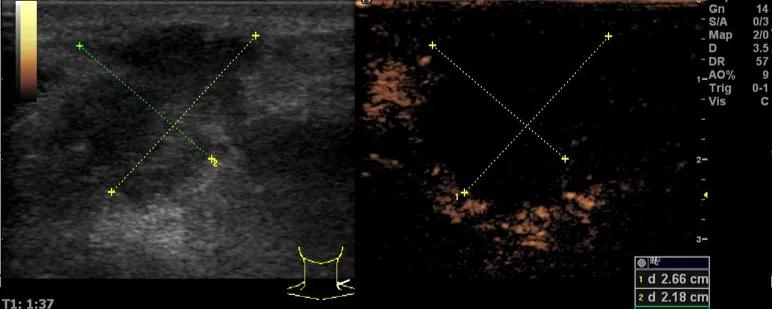

第二例是食管癌患者,术后半年余锁骨上固定淋巴结可触及肿大,疼痛非常明显,系统治疗后无缓解,患者希望通过局部处理缓解症状。造影显示强化信号明显,结节部分区域坏死,故主要针对强化区域从后向前的逐层的消融,皮下进行液体隔离减少烫伤。热消融后影像显示血流增强消失,弹性、硬度增高,一个月后复查显示充盈缺损,完全消融,疗效远超预期。

(病例2图例)